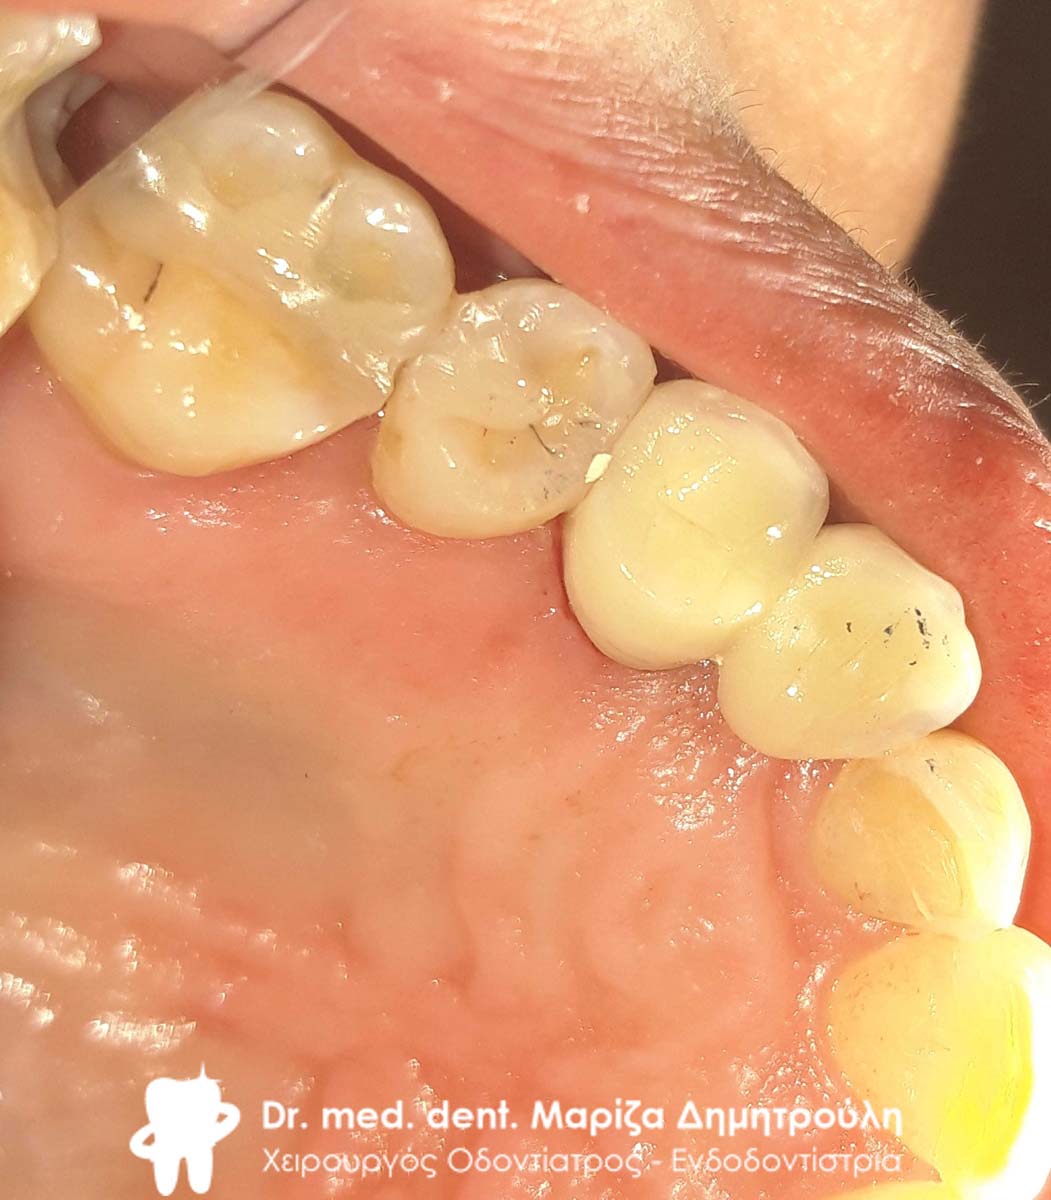

Τελική κλινική εικόνα του ολοκεραμικού ένθετου στον προγόμφιο